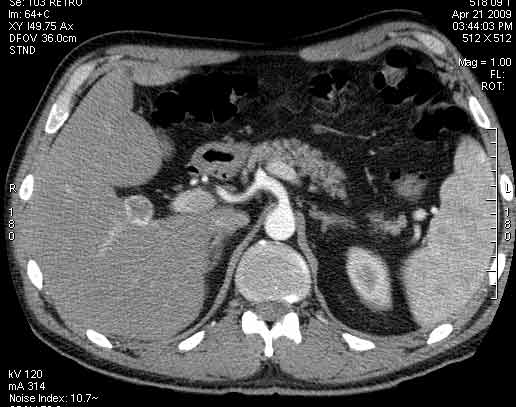

Сонограммы, КТ- артериальная, портальная и отсроченная паренхиматозная фазы

Сделали КТ (весьма похвальная тактика); по КТ: в артериальную фазу: периферическое усиление в виде сливающихся островков контраста, с центрипетальной направленностью. Венозная и отсроченная фаза-хорошее накопление контраста; образование практически изоденсно по отношению к паренхиме печени. Классика гемангиомы. Вуаля-диагноз на "тарелочке".

Вывод: надо иметь ввиду, что эхогенность это относительное понятие, эхогенность гемангиомы может изменятся при изменении положения обследуемого пациента (см. прикреплённую статью); не надо забывать что эхогенность образование это понятие относительное, т.е. относительно окружающей паренхимы печени! При стеатозе, гемангиома может выглядеть гипоэхогенно по отношению к гиперэхогенной паренхиме окружающей печени. И главное, есть сомнение-заказываем таргетное мультифазовое КТ.